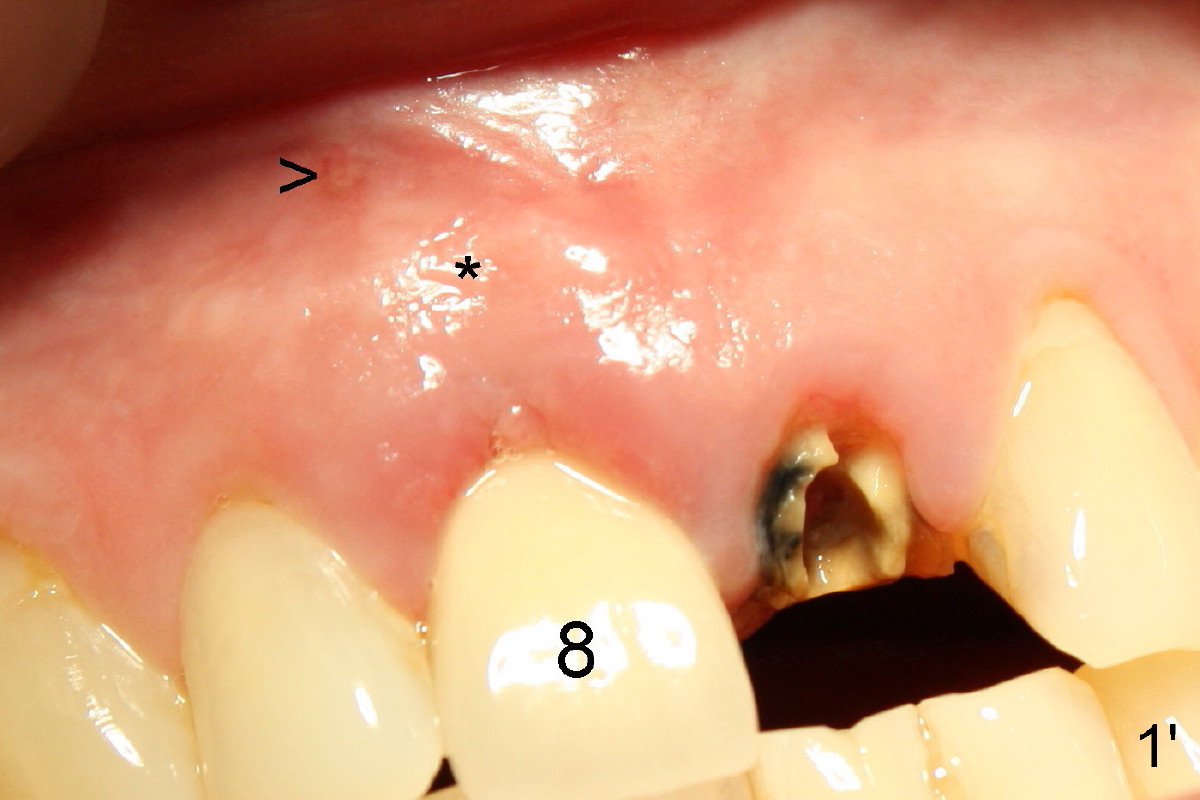

X-ray in Fig.13 is taken two months after implant removal and immediately before 2nd implant placement.  Round tapered osteotomes (2 and 3 mm) are inserted into the socket.  Then a 4.5x20 mm tapered tap (Fig.14: T) is driven into the socket first by a slow handpiece and second by drill/tap extender (without wrench).  Finally a 5x20 tapered implant is torqued into the recipient socket with some degree of resistance (Fig.15: I).